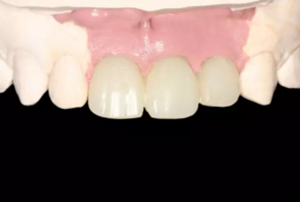

圖1 術(shù)前微笑像

圖2 術(shù)前口內(nèi)像